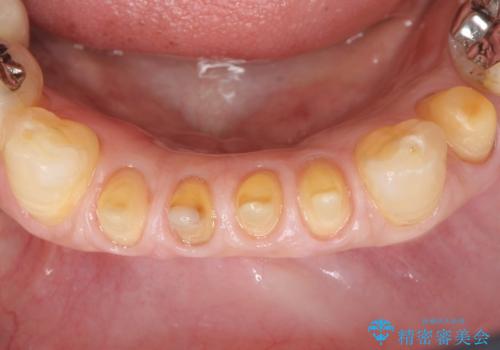

元気なうちに治療しておきたいという患者様の強いご希望により、下顎前歯の連結補綴と欠けている小臼歯の補綴治療を行いました。

自然な仕上がりに喜んで下さいました。

クラウンを連結することにより気にされていた動揺もなくなり、安心して頂けました。

被せ物の種類:オールセラミッククラウン スタンダード